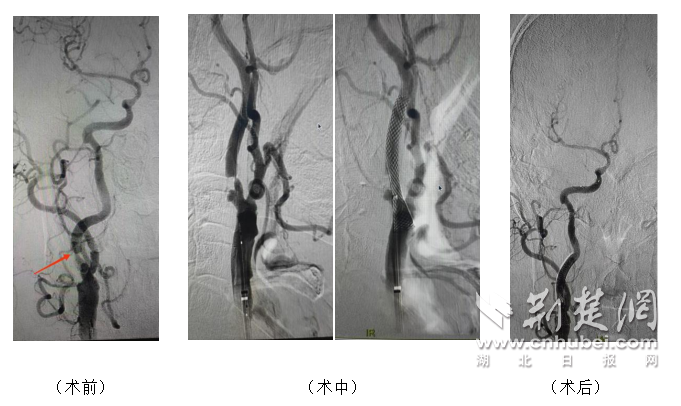

图为武汉市第五医院专家团队采用微创手术进行血管造影。

手术当天,局部麻醉下,神经内科张细柳主任带领的介入团队在数字减影血管造影(DSA)引导下,通过腹股沟小穿刺点将导引导管精准放置在狭窄部位。团队完成了脑保护装置的放置、扩张前球囊扩张、支架精确释放、扩张后球囊粘附优化等一系列关键步骤。将每个流程中的操作错误管理至毫米级。术中血管造影显示狭窄的血管成功扩张,脑部血流恢复,患者全程保持清醒。程序。没有任何不适。